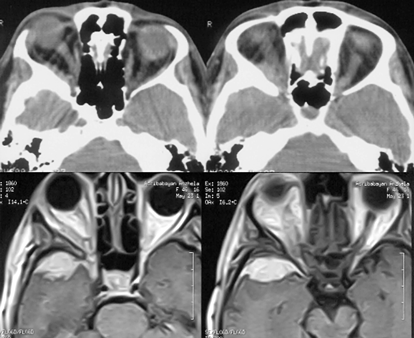

Рисунок 4. Менингиома площадки основной кости. МРТ, Т2-взвешенные изображения, КТ (слева внизу) с контрастным усилением

Менингиомы площадки основной кости (рис. 4)

Развиваются кзади от “петушиного гребня”. В клинике превалируют зрительные нарушения, вызванные сдавлением зрительных нервов. Оптимальный хирургический доступ к ним — односторонний субфронтальный. Техника удаления этих опухолей практически не отличается от описанной выше. Сложности возникают при врастании опухоли в зрительные каналы, в этих ситуациях радикальное удаление инфильтрированной ТМО не представляется возможным, производится декомпрессия каналов зрительных нервов с удалением доступной части опухоли.